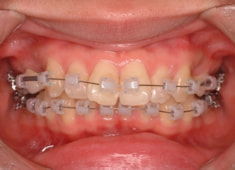

治療後(1年9ヶ月後)

治療開始から1年7ヶ月後